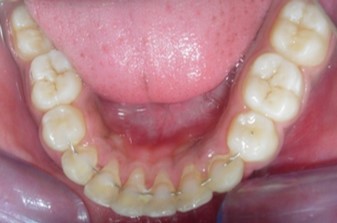

Radiographic assessment. The panoramic radiograph confirmed the presence of all permanent teeth with the presence of 18, 28, 38 and 48 tooth germs with normal alveolar bone levels. (Figure 2).

Figure 2.Pre-treatment panoramic radiograph